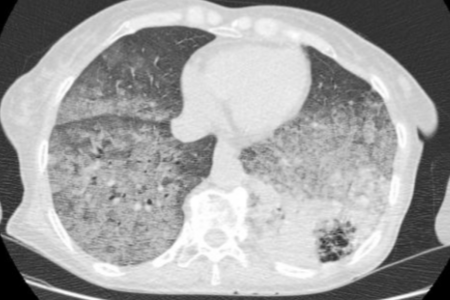

顾兴主任医师:发病过程长达半年,无发热、盗汗,未发现凝血异常或双下肢深静脉血栓,不考虑肺栓塞;阅片可见该患者双肺可见片状磨玻璃影,左肺下叶可见条片状高密度影,期内可见支气管影及边界不清类圆形透亮空洞影,该空洞无晕征、反晕征、新月征、曲霉球等表现,不符合曲霉菌感染的特点。需考虑肺炎型肺癌的可能性,可请肺穿小组评估肺穿刺活检风险性。

7月10日, CT引导下的经皮肺穿刺活检,病理报告最终确诊患者患有粘液腺癌。

图:2024-7-10 CT引导下经皮肺穿刺、2024-7-12肺穿刺活检病理

评论:什么是肺炎型肺癌?

肺炎型肺癌是一种影像学上表现为实变、斑片或大片状模糊阴影的肺癌。它属于周围型肺癌,病理类型多见于肺腺癌,尤其是粘液腺癌。粘液腺癌是一种原发性肺腺癌的变异型,起源于细支气管壁以远的支气管与肺泡上皮,早期表现为单发结节,中后期会出现斑片状实变和磨玻璃样的肺炎影像学改变。随着粘液腺癌体量的增大和粘液的播散,临床上会有咳白痰的症状,痰液脱落细胞中可见肿瘤细胞。早期无远处转移的患者,手术治疗为首选;对于广泛转移的患者,可通过化疗、靶向或免疫治疗来抑制肿瘤生长。

该患者的经历提醒我们,在胸部CT提示双肺大片磨玻璃样渗出及大片实变影,提示“白肺”,初期的真菌检查(曲霉菌、耶氏肺孢子菌、光滑念珠菌)对医生带来很大的误导,在调整抗生素无效的情况下,一定要反复推敲、思路开阔,想到肺炎型肺癌的可能。